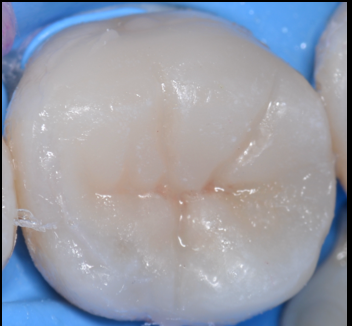

治療前

治療後